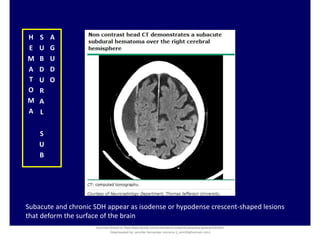

Subacute and chronic SDH appear as isodense or hypodense crescent-shaped lesions

that deform the surface of the brain